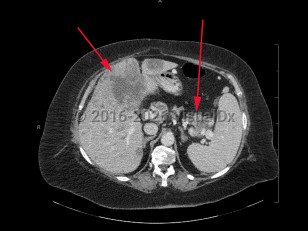

Abdominal aortic aneurysmAbdominal aortic aneurysm

Aortic dissectionAortic dissection